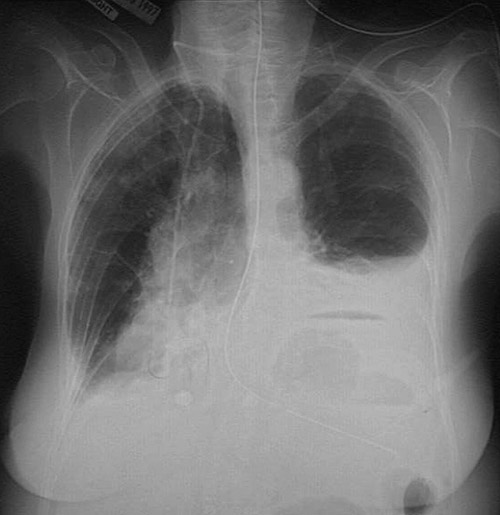

![]() | This radiograph demonstrates fluid in the left pleural cavity. This pleural effusion could result from a transudate (serous effusion) or from hemorrhage (hemothorax), or serous fluid tinged with blood (serosanguinous effusion). This effusion could be chylous (which is quite rare). A purulent exudate at this location may be termed empyema. An air-fluid level is seen in the stomach below the dome of the left diaphragmatic leaf. |